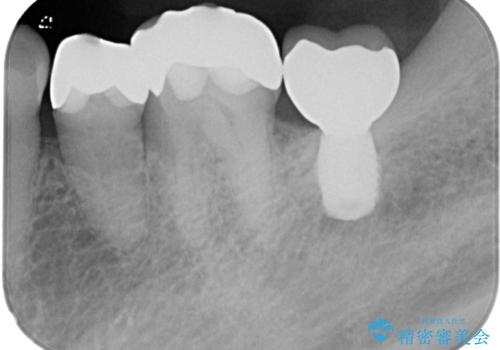

- 左下奥歯のインプラント治療と左上の被せもののやり替えを希望されて来院された患者様です。

左上の奥2本は他院で根管治療と仮歯まで入れている状態です。根管治療のやり替えは希望されなかったため被せものから治療していくことにしました。

その手前の小臼歯は根尖病変が認められるため根管治療のやり直しからしていくこととしました。

左下はインプラントによる補綴治療を行いました。

左上の小臼歯は根尖病巣が大きかったため、今後も定期的にレントゲンを撮り、経過観察していく予定です。